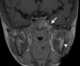

Sickle cell disease with bone infarction